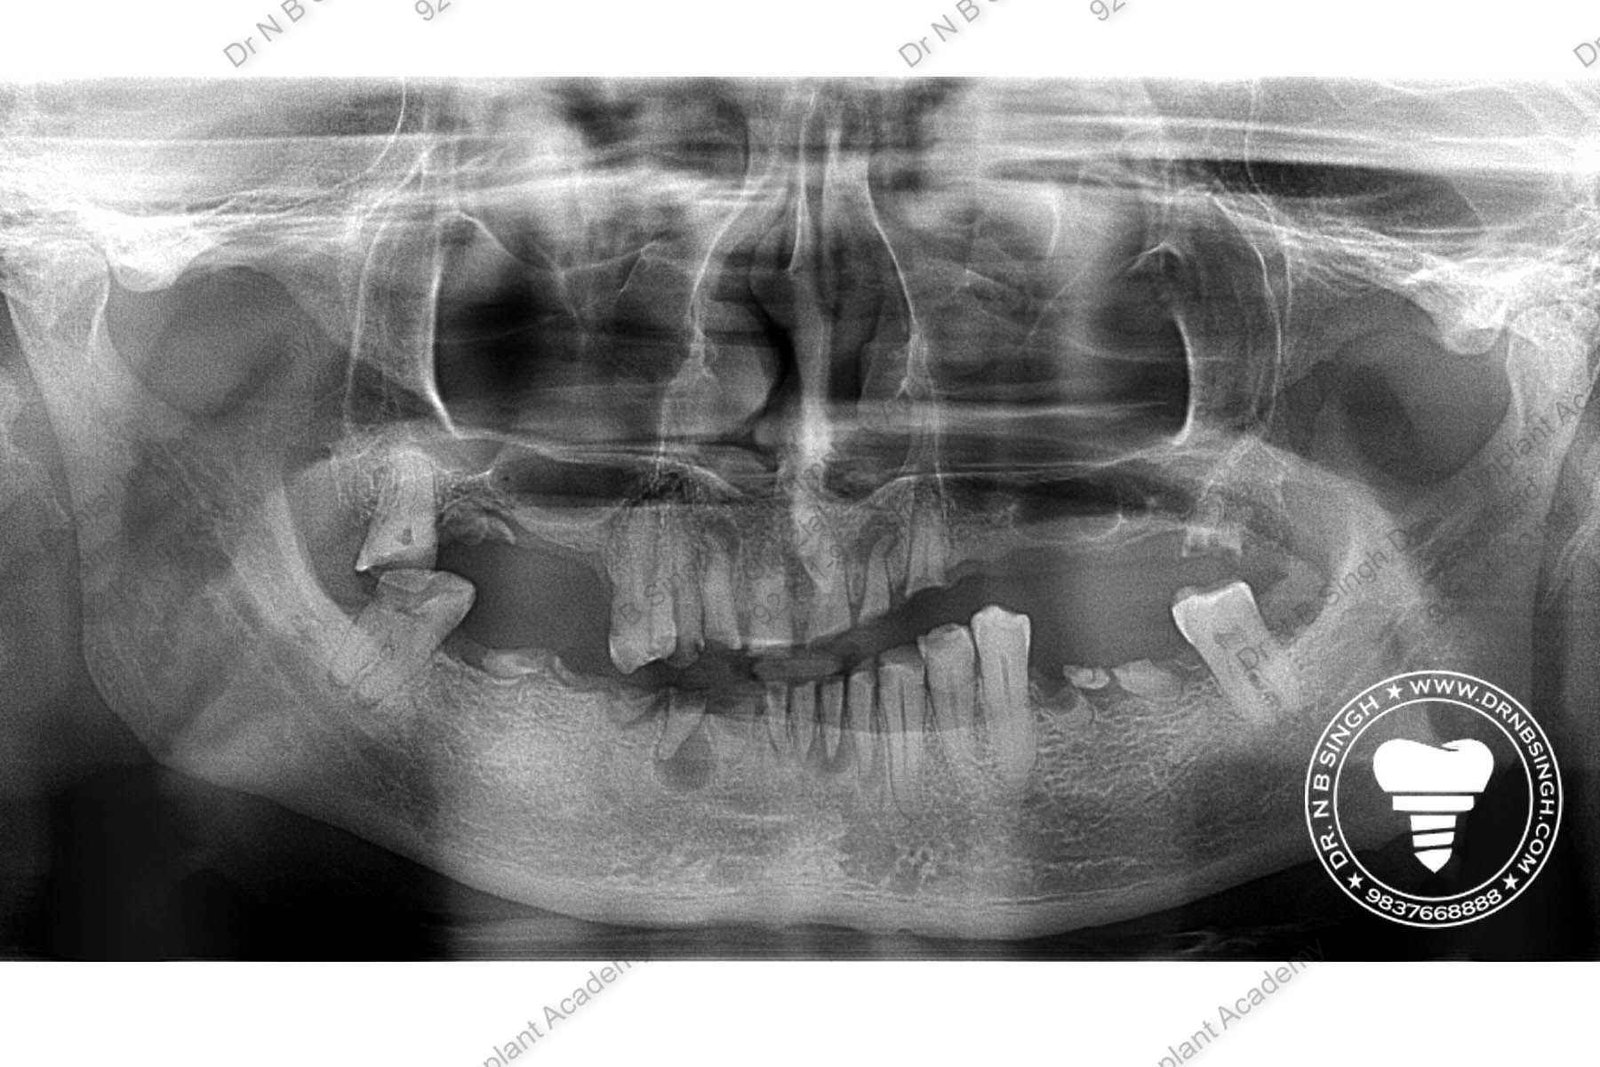

C1005 zygomatic basal implant full mouth – Ali Hasan 4